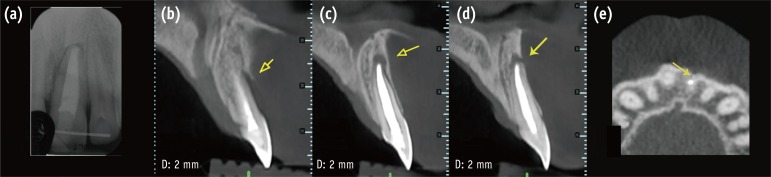

A clinical examination showed a moderate swelling on the vestibular side in the region of tooth #21, as well as the presence of a sinus tract in the same area, approximately 4 mm from the gingival margin (Figure 1). A narrow periodontal defect 7 mm in depth was present on the buccal side, as evaluated using a periodontal probe. A radiographic examination performed before surgery using both periapical radiographs and CBCT (J. Morita MFG Corp., Kyoto, Japan) revealed a root-end resection, a periapical radiolucency, and a widening of the periodontal ligament space at the mesial aspect of the root, although no hair-like fracture line radiolucency was noted in the tooth, except in the CBCT horizontal projection that showed an incomplete VRF 3 mm from the apex (Figure 2).